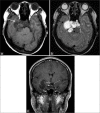

Figure 7:

(a) Plain CT cervical spine. Cervical spine tumor at C2–C3 levels. It was associated with prevertebral soft-tissue mass spanning across C2–C4 levels with intratumoral calcifications within (white arrow). There was epidural involvement at the anterior epidural space (black arrow). (b) Plain CT cervical spine. Bone destruction at C2 and C3 vertebrae. (c) Plain CT cervical spine. Involvement of the right C3 neuroforamen.

Figure 8:

Contrast CT cervical spine. Encasement of the right vertebral artery which remained opacified (black arrow).

Figure 9:

(a-c) MRI cervical spine. A T1-weighted hypointense and T2-weighted hyperintense cervical spine tumor with mild contrast enhancement. (d) The mass extended into and obliterated the anterior epidural space, demonstrating a draped curtain sign (white arrow). Normal T2-weighted flow void pattern of the right vertebral artery was preserved (dotted arrow).